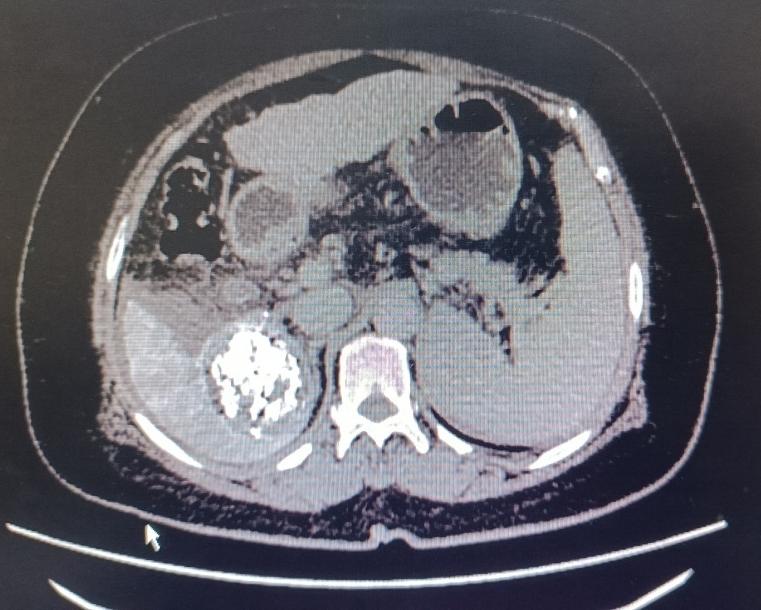

患者女性,57岁,3月12日,突发腹部疼痛就诊于当地医院,CT示肝肿瘤破裂出血,随即转入市中心医院急诊科,分诊后入住普外科二病区。急查实验室检查示:血红蛋白71g/L,血压85/60mmHg左右,正值周日,值班人员电话紧急请介入科会诊,经分析,患者随时有失血性休克风险,当即立断启动疫情状态下的急危重症患者介入诊疗绿色通道。应急值班人员第一时间到位,行肝动脉造影明确了出血动脉(部位),现场评估并制定了手术方案,对肿瘤出血进行了封堵及TACE,术后给予止血、保肝、输血、抗感染等对症处理,病情稳步好转。复查CT肝内碘油沉积良好(提示介入治疗疗效佳),目前已安全出院。

该患者诊断及时,采取介入治疗迅速有效,避免了外科开腹手术,减少了创伤。